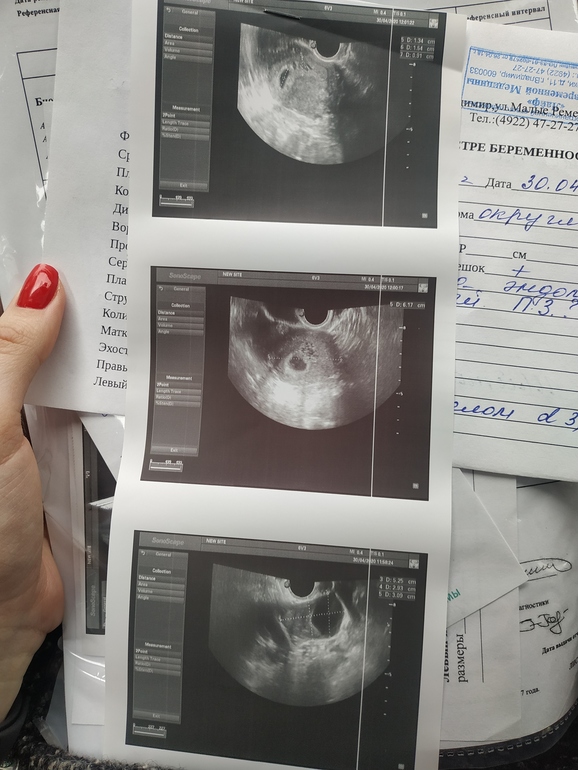

У меня завтра повторное УЗИ, я боюсь очень туда идти... Но у меня думаю не ошибка, прям явно видны пузыри рядом с ПЯ( первое и второе фото